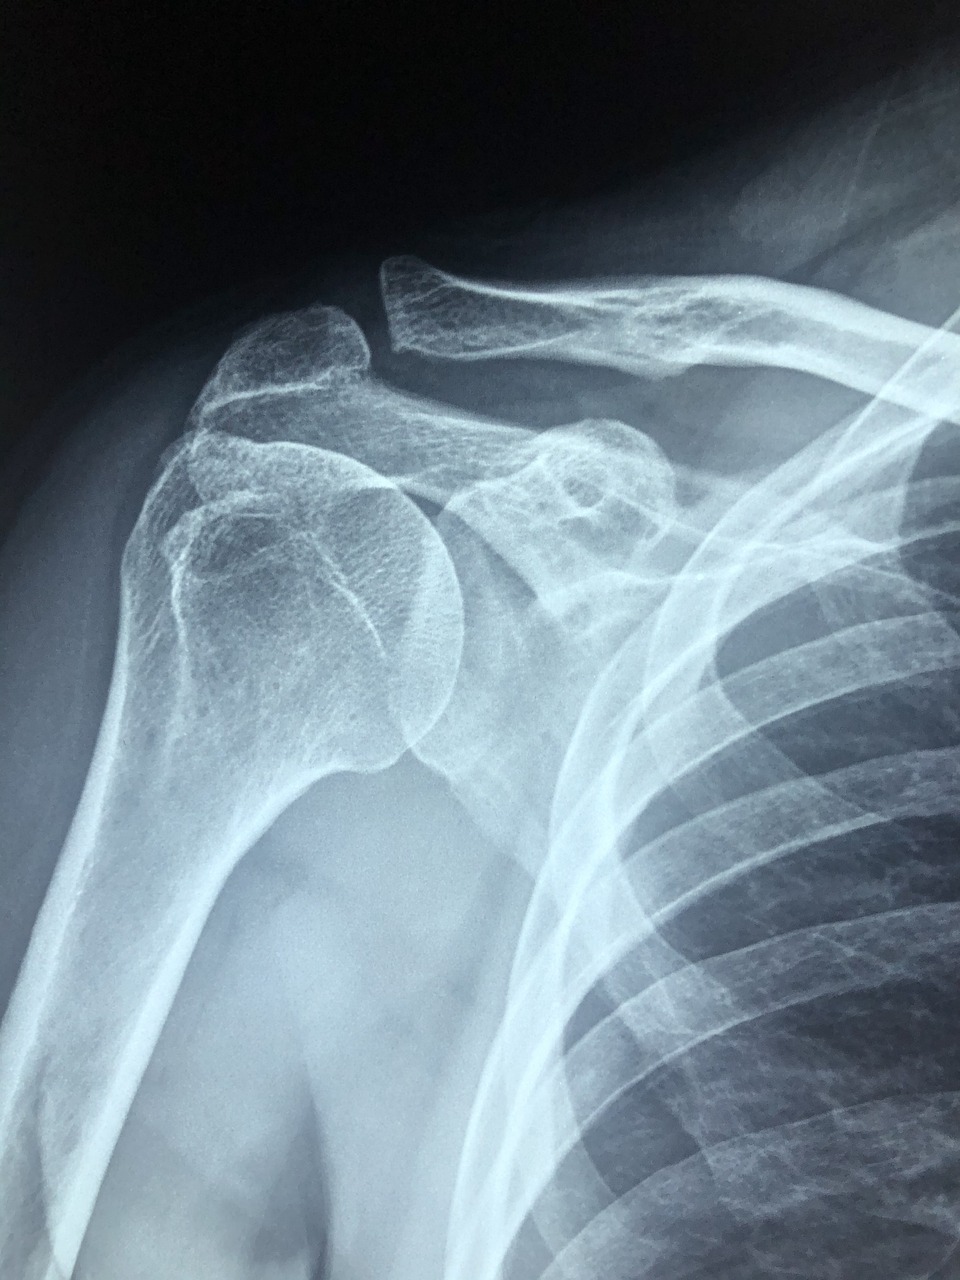

석회화건염은 어깨 관절 초음파나 X-ray 검사로 쉽게 진단할 수 있습니다.

어깨가 아프다면 병원에서 검사를 받아보는 것이 빠른 치료의 시작입니다.